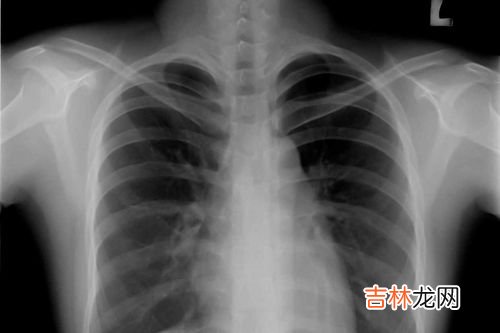

若患者出现咳嗽的症状后及时就诊,检查X线胸片上发现,肺门不清、肺门增大等的情况 , 也可以做肺CT检查 , 来协助进一步的明确诊断 。除此之外 , 还有咳嗽激发试验和呼出一氧化碳 , 是呼吸系统最常见的检查 。

肺部CT一般都是有确诊肺部疾病或癌变 , 或者临床症状怀疑肺部疾病或癌变 , 或者是通过其它影像手段比如拍X光片后发现异常后才做的 。